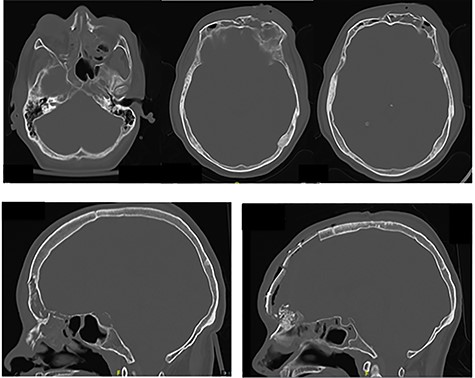

A 38-year-old man presented to the emergency department at our level-one trauma center following a high-speed motor vehicle accident. Initial trauma workup revealed significant anterior and basilar skull base fractures (Fig. 1) as well as multiple orthopedic injuries (pubic ramus fracture, clavicular and humerus fracture) and intrathoracic and abdominal injuries (piriformis muscle contusion, retrosternal hematoma and pulmonary contusion). He was ultimately hemodynamically stabilized and underwent orthopedic repair. Throughout his hospitalization, the patient’s neurologic status remained stable. He was closely monitored by the neurosurgery and plastics services for development of a cerebrospinal fluid (CSF) leak.

(A, B) Preoperative CT imaging showing extensive anterior and skull base fractures. The patient ultimately developed a cerebrospinal fluid leak and required operative repair. (C) Postoperative CT imaging showing bifrontal craniotomy repair as well as repair of the anterior skull base.

On hospital Day 5, the patient developed a profuse CSF leak requiring a lumbar drain was placed. Subsequently, after failure of the lumbar drain to completely stop the rhinorhea in 48 hours, the patient was taken to the operating room with both plastic surgery and neurosurgery for a bifrontal craniotomy for cranialization of the frontal sinus via split calvarial bone graft and periosteal flap. At that time he also underwent repair of naso-orbitoethmoidal fractures (Fig. 1A and C). His postoperative course was uncomplicated. On hospital Day 9 (postoperative Day 2), the lumbar drain was clamped and removed after there was no further evidence of CSF leak in 24 hours. He was ultimately discharged on hospital Day 10.